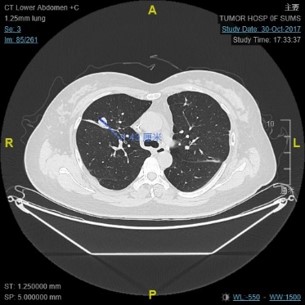

胸腹盆CT: 双肺转移

影像学诊断:直肠癌术后肺转移

初诊 左肺转移消融后